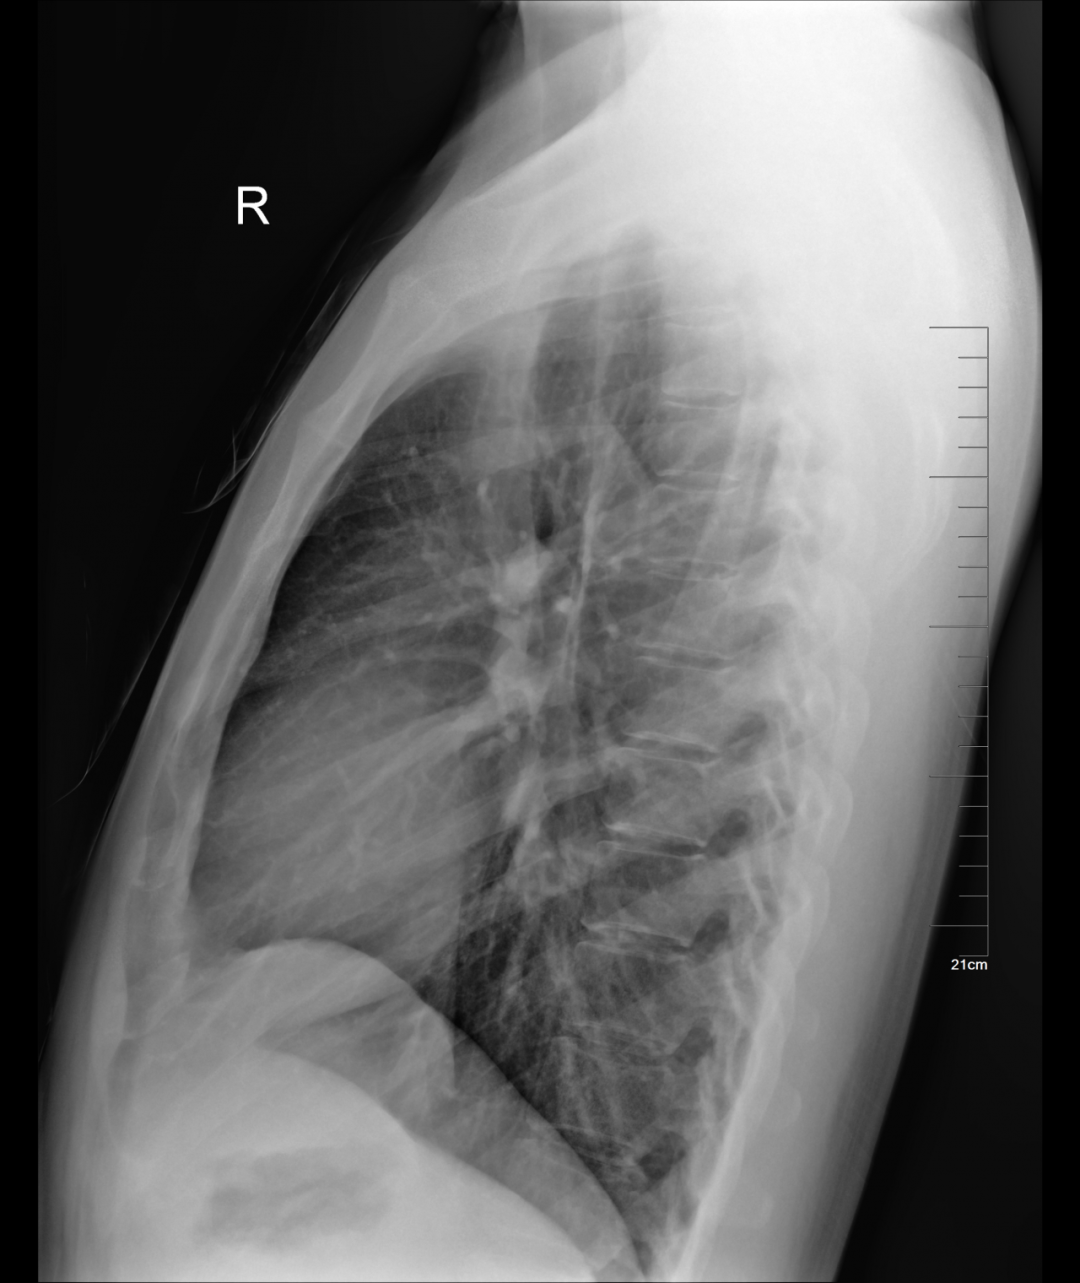

一、DR检查是在普通X光拍片的基础上,发展成为数字化X线拍片,通俗一点来理解,就是传统X光的进阶版,但本质还是差不多的,主要还是利用X射线的穿透性原理。虽然检查部位和普通X光拍片都一样,但DR的图像分辨率明显比X光高,放射线辐射剂量也降低了非常多。人体组织结构由不同元素组成,单位体积内的各种元素的总量就是密度,例如骨骼、钙化灶等听起来较为厚重的组织,所吸收的X光较多,穿透人体中余下的X线量较少,因此形成白色影像,也就是传说中的“高密度影”,像是呼吸道、胃肠道等听起来质地疏松的部位,所吸收的X光较少,在影像学上呈现的是黑色影像,即“低密度影”。DR成像环节少,速度也快,图像清晰细腻,医生可根据根据自身需要,获得更多的诊断信息。DR图像动态范围广,有很宽的曝光宽容度,因而容许拍摄中的技术误差,即使在一些曝光条件难以掌握的部位,也能获得很好的图像。总体来说,DR是最传统也是最低价的影像检查,是很多疾病的首选检查。

DR最常用于人体胸部及骨骼摄片,也可拍摄其他部位,例如腹部、牙齿、头颅等。使用人群较广,可以进行全身各部位检查,曝光后10秒就可获得数字影像,成像速度快,且价格便宜,极大提高了工作效率,方便临床重症、急症患者的诊治。但DR受制于深浅组织影响的互相重叠和隐藏,有时需要多次或多角度的拍摄才能看清。